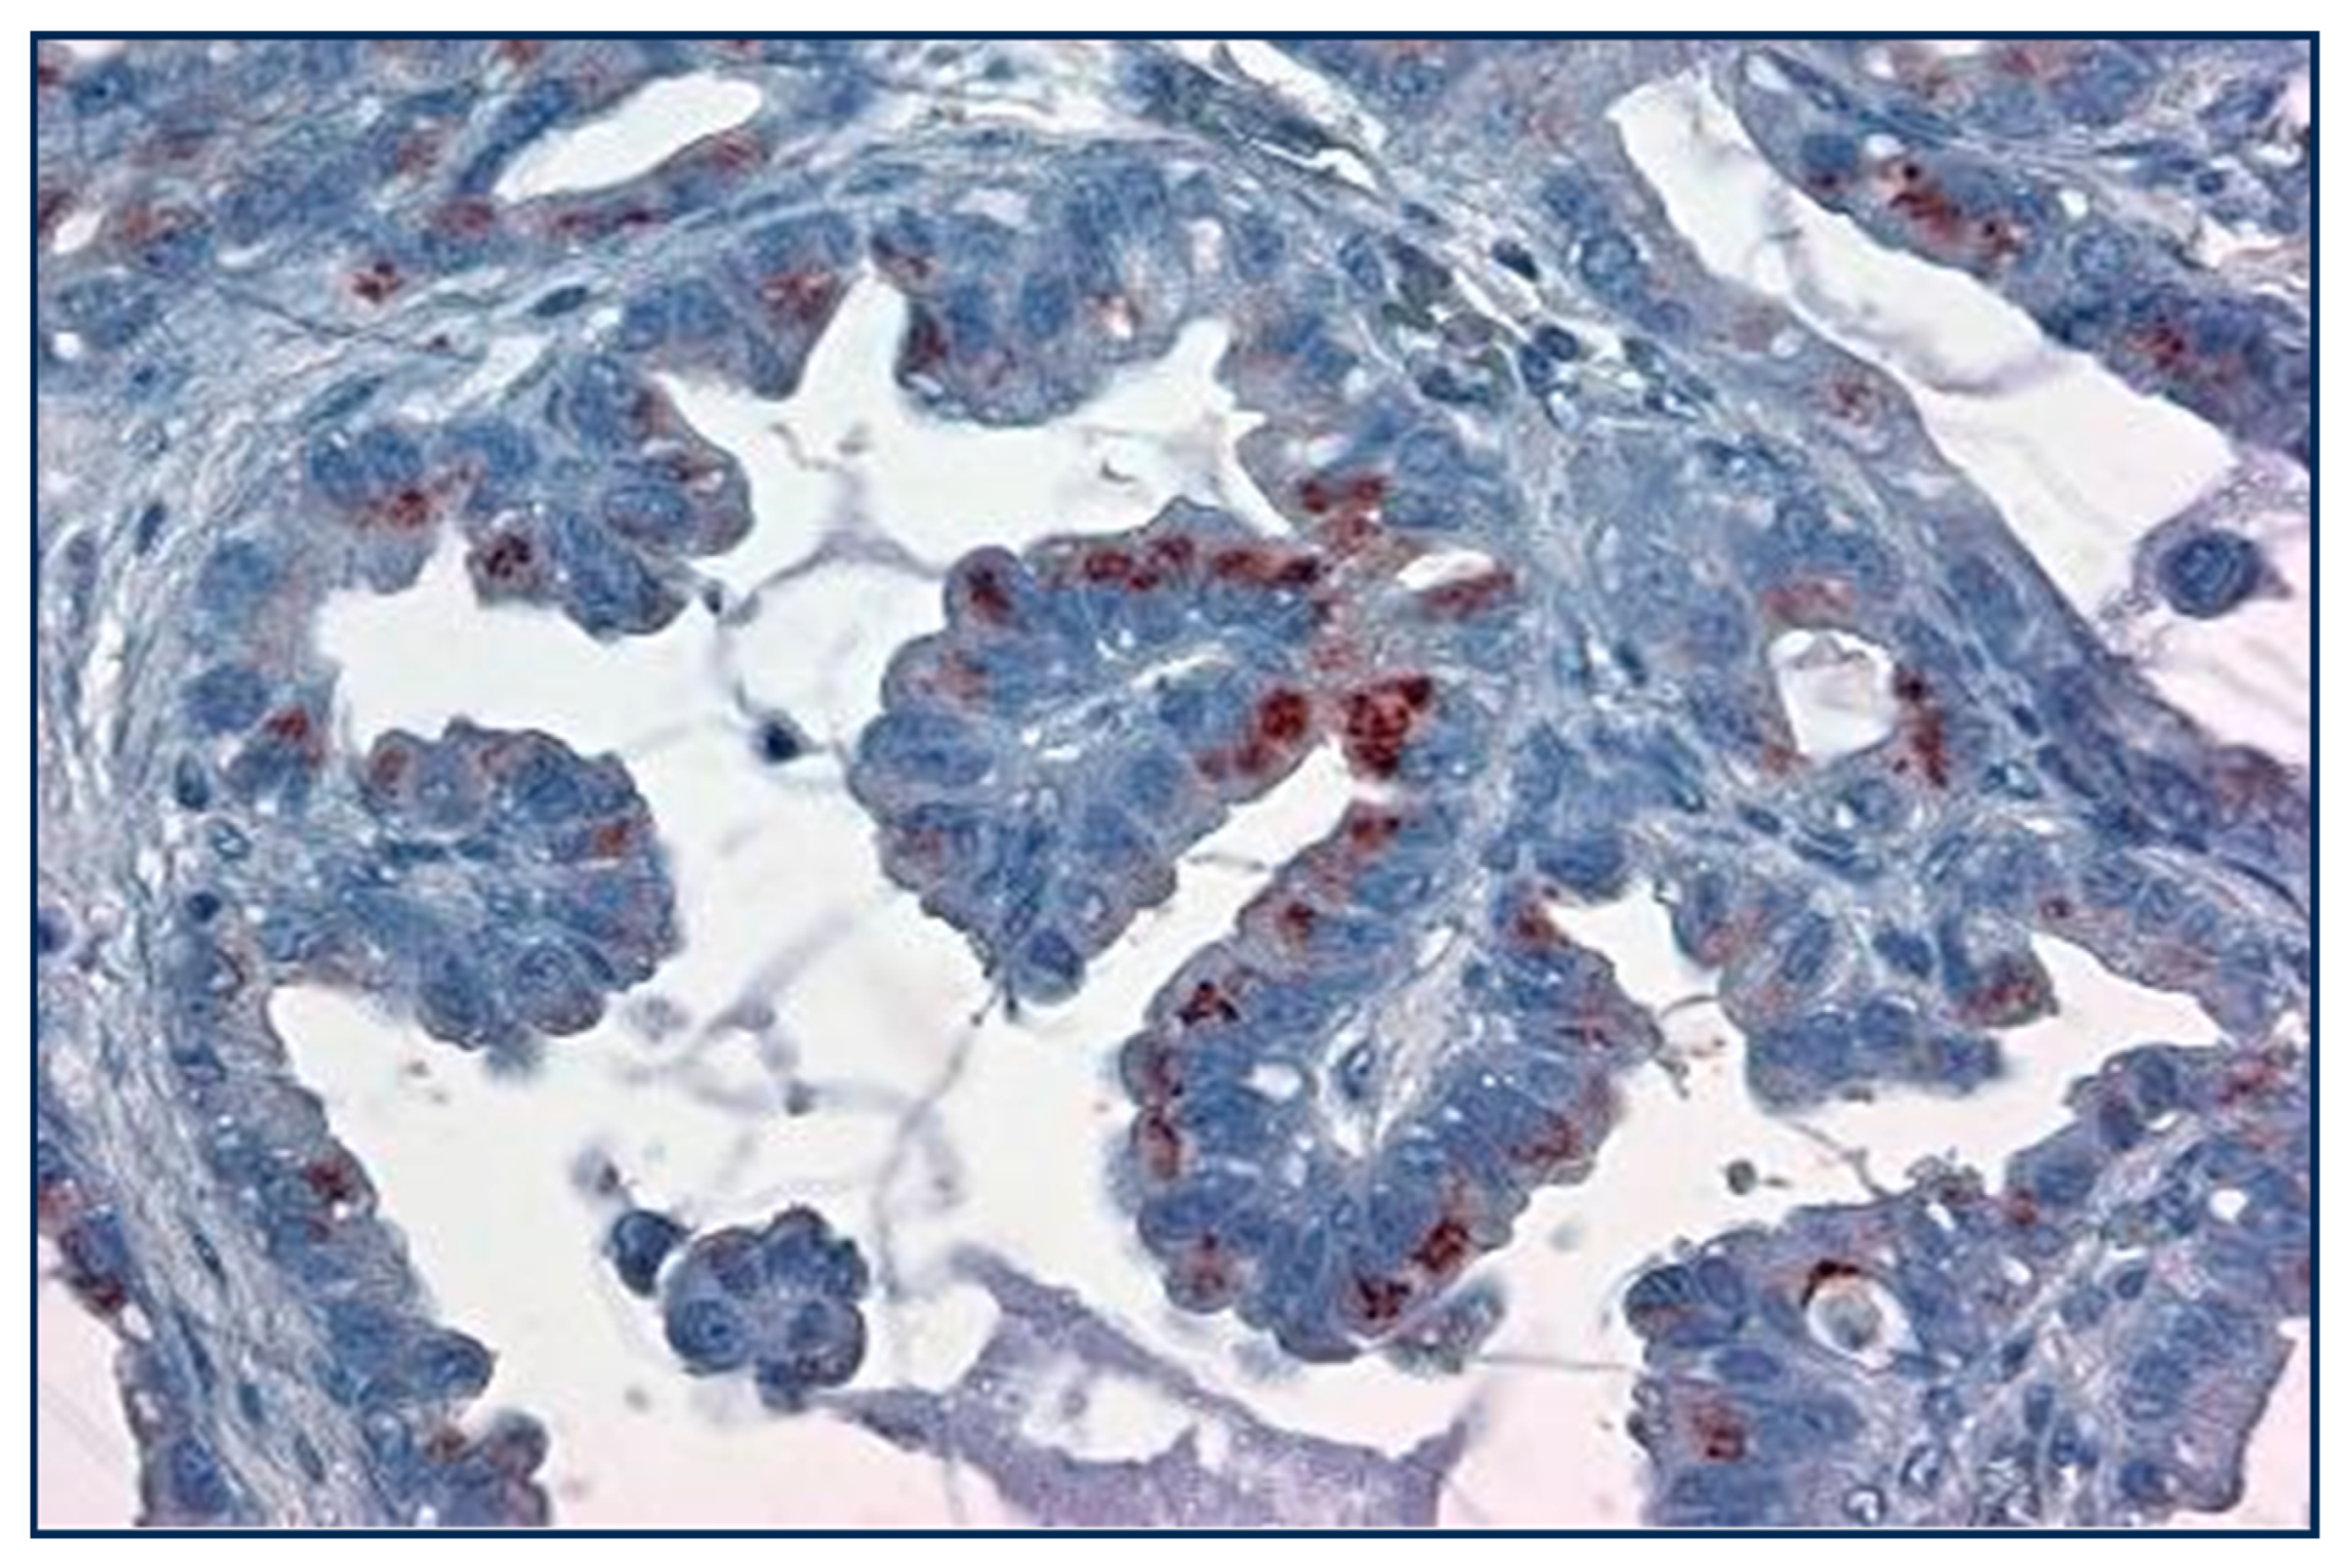

| Lepidic/BA | 67 | N/A | N/A | ||

| AdenoCa | 32 | 80 (muc10–15) | N/A | 20–30 | 94–100 |

| Papillary | 74 | N/A | |||